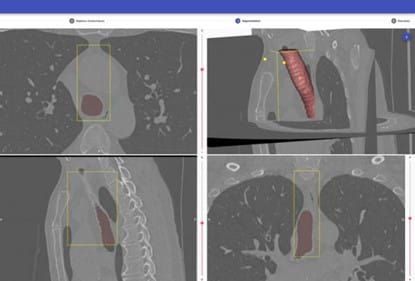

Lorsqu’un praticien estime qu’une trachéotomie est indispensable pour un patient, il lui fait passer un scanner, afin d’obtenir un modèle 3D exact de sa trachée en vue de sélectionner ou de concevoir la canule la plus adaptée. « Mais la géométrie 3D ne suffit pas. Nous ne sommes pas sur de la mécanique ‘‘dure’’ où il s’agit d’enfiler un tuyau dans un conduit rigide. La trachée est une structure vivante, souple et déformable qu’il ne faut pas léser mécaniquement. C’est pourquoi nous avons dû développer, avec des ingénieurs bio-mécaniciens, un logiciel ‘‘métier’’ spécifique, dont le procédé est aujourd’hui breveté. Il s’agit en fait, à partir de l’imagerie 3D et de critères physiologiques propres à chaque patient introduits par le praticien, de paramétrer des modèles de trachées existants en bibliothèque, afin d’obtenir rapidement un jumeau numérique 3D bio-mécanique exact de la trachée du patient. ».

Le logiciel cherche dans la base de données de canules standard du marché, celle qui est la plus adaptée à la trachée du patient. C’est alors un outil d’aide à la décision pour sélectionner un équipement. « Il permet aussi de s’assurer que le mouvement d’insertion de celle-ci ne génèrera pas de lésions délétères pour le patient. »

Si aucune solution standard ne convient, le logiciel définit alors la forme optimale de canule compatible avec la trachée du patient, tant du point de vue géométrique que physiologique. Ce modèle 3D servira à la fabrication d’une canule sur-mesure propre au patient.

La trachéotomie, procédure chirurgicale la plus fréquemment réalisée en réanimation, permet un sevrage de la ventilation par la possibilité d’une ventilation trachéale directe via des canules. L’inadéquation entre la canule et le patient reste, à ce jour, la principale cause de complications. Il faut donc minimiser les conflits mécaniques pour diminuer les complications médicales. D’où la création, à partir de l’imagerie 3D et du savoir-faire physiologique des praticiens, via la modélisation et la simulation 3D in-silico, d’un véritable jumeau numérique bio-mécanique de la trachée, afin de sélectionner ou concevoir des canules parfaitement adaptées à chaque patient. |